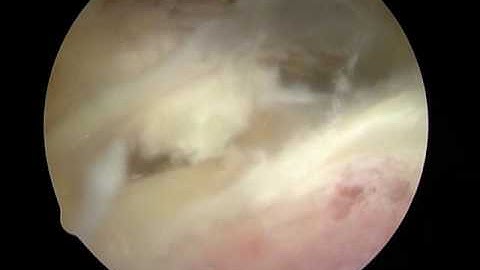

Arthroscopic Suprascapular Nerve Decompression